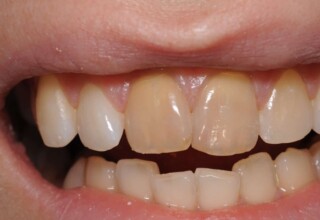

Composite Resin Veneers

Resin veneers are an inexpensive mode of esthetic improvement of anterior teeth, premolars also. Their potential is admirable and their limit is the operator’s clinical dexterity and imagination. In this case there were multiple problems with the upper four incisors: staining, poor inclinations, diastemas, multishading, poor interrelationship and poor tooth-gingiva ratios. They were restored with four direct composite resin veneers (one on a porcelain implant crown!) which were manufactured intraorally!!!